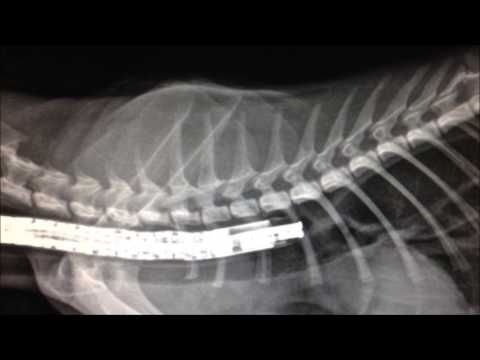

Баллонная дилатация пищевода у кота с помощью эндоскопа.

Что такое стриктура пищевода и как это устранить увидите в нашем видео. Процедуру провели хирурги ветеринарной клиники "Эксвет" Алексей Португейс и Владимир Юсипов, анестезиолог Евгений Белецкий.